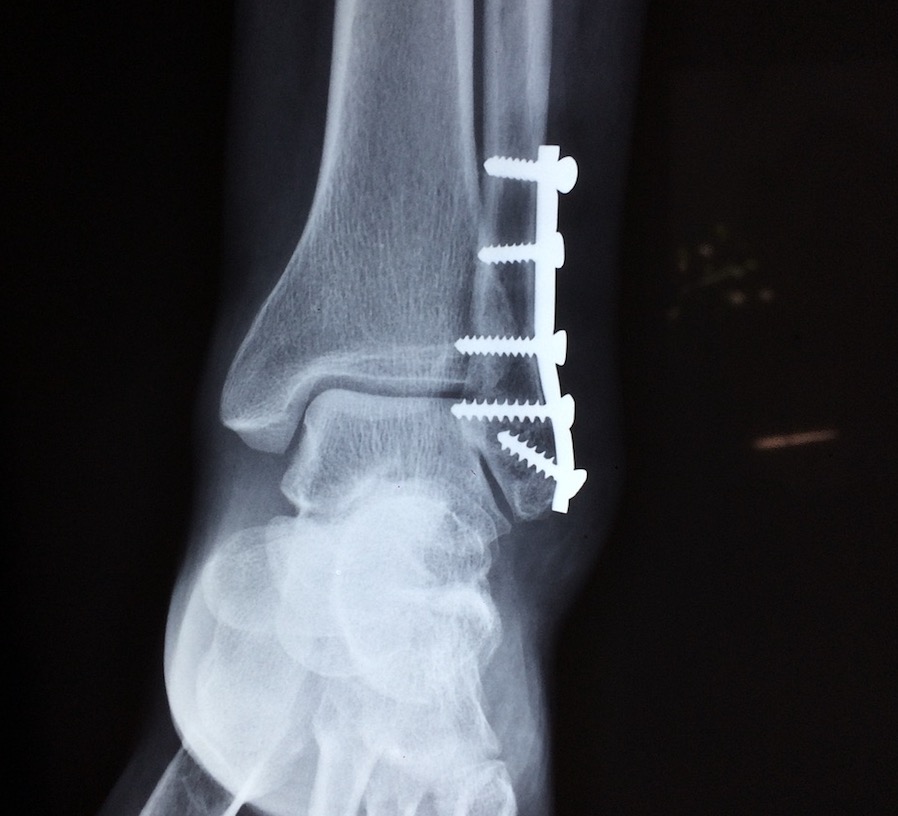

Adultos com fraturas de fragilidade;